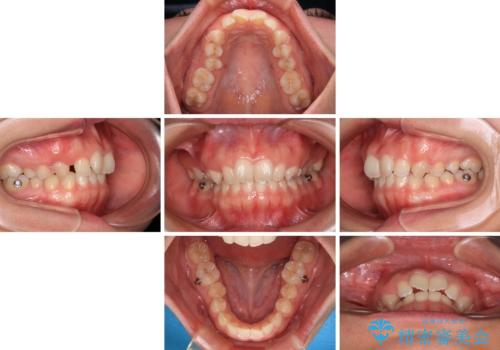

インビザライン単体でも同様の結果が得られる可能性がありますが、万が一奥歯がうまく後方移動できなかった場合、リカバリーが非常に大変となるため、事前に補助装置を併用して確実に結果が得られるように工夫をしています。